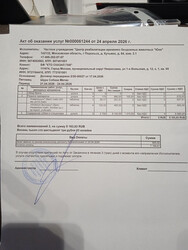

Всё оказалось совсем не так, как мы планировали. Мы поехали с бедром, аспасать пришлось колено.

Операция была на порванную коленную связку - левое колено. Это было выявлено

при дополнительном обследовании.

Само колено не ахти, разрушается. В него была введена половина дозы препарата

Noltrex (чек прилагается).

Правое бедро тоже разрушается, но доктор сказал его не трогать, если не

беспокоит. В него введена 2ая половина препарата.

Действие препарата от года до 5 лет. Можно им поддерживать. Контрольный рентген сделают, когда приедет в приют. Ограничение подвижности 3 нед, потом можно в вольер.

32 635 ₽ операция

17 250 ₽ анестезия

3 080 Р стационар

6 276 ₽ куплен Noltrex

1 840 Р лекарства по назначению хирурга

ИТОГО 61 081

24 апреля мы поехали домой! В смысле в приют, который Шура считает своим домом, пока другого ей никто непредложил. Счёт за дни в Юне с 21 по 24 апреля на сумму 8163,83 ниже

Наконец то свели все цифры по затратам на операцию для Шурочки:

РАСХОД:

-Ветлайф 52965

-лекарства 8116

-Юна 27168,81

————————

Всего 88 249,81₽

СПАСИБО ОГОРОМНОЕ всем, кто помогает.    Вся сумма, потраченная на операцию Шуре, собрана, долги закрыты! Вся сумма, потраченная на операцию Шуре, собрана, долги закрыты!